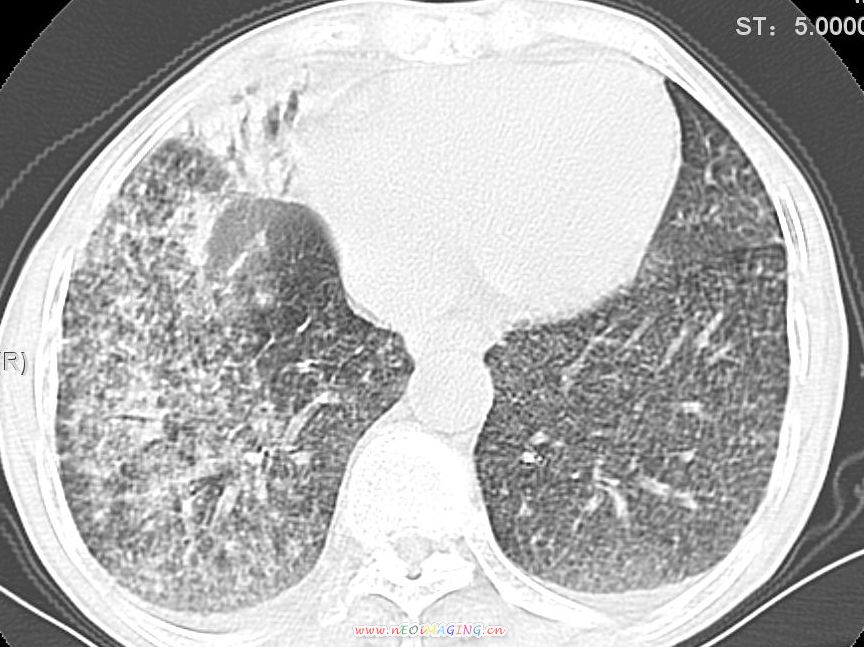

患者咳嗽月余,高热数天,咳黄色稍脓痰。

高热数天,咳黄色稍脓痰,肯定应该有急性化脓性感染,左上叶舌段及右肿叶可见多量斑片状及支气管气像,首先考虑肺部感染合并血型播散性肺脓肿(脓肿为早期改变),其次不排除有肺泡癌,第三不排除结核,建议治疗后复查

双肺野分布多个小结节状高密度影,其内散在斑片状模糊影,气管。支气管通畅,纵隔内淋巴结钙化,胸膜局限性增厚粘连,胸腔少量积液。结合病史考虑结核并感染的可能性大,胸膜炎并积液。肺泡癌待排。

亚急性血行播散型肺结核合并肺内感染